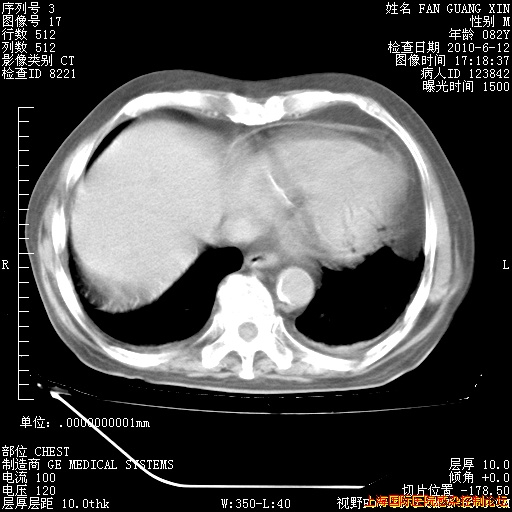

6月12日纵膈窗

海管,自昨日你和我通完话后,不知您岳父消化道症状有无缓解?体温怎样?阅读7.12日胸部ct,个人认为目前激素治疗是有效的,甲强龙减量是适宜的。因在抗痨治疗,需密切观察肝功、肾功能和血常规。不过,老年、长期住院和大量使用激素,很担心菌群失调发生